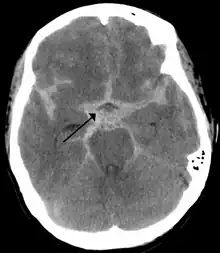

Selected image –

T1-weighted MRI scans (with contrast) of the same brain slice at monthly intervals. Bright spots indicate active lesions of multiple sclerosis.

Photo credit: Public domain (U.S. Brookhaven National Laboratory)